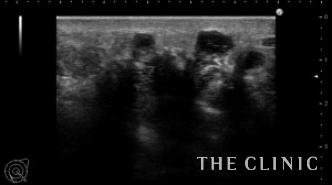

エコーでは多数のヒアルロン酸のしこりを認め、皮膚の発赤部分の深部は炎症のため診断できませんでした。

MRIでは多発するヒアルロン酸が見られます。左胸の乳腺組織の下には炎症の原因と思われる液体が貯留しています。